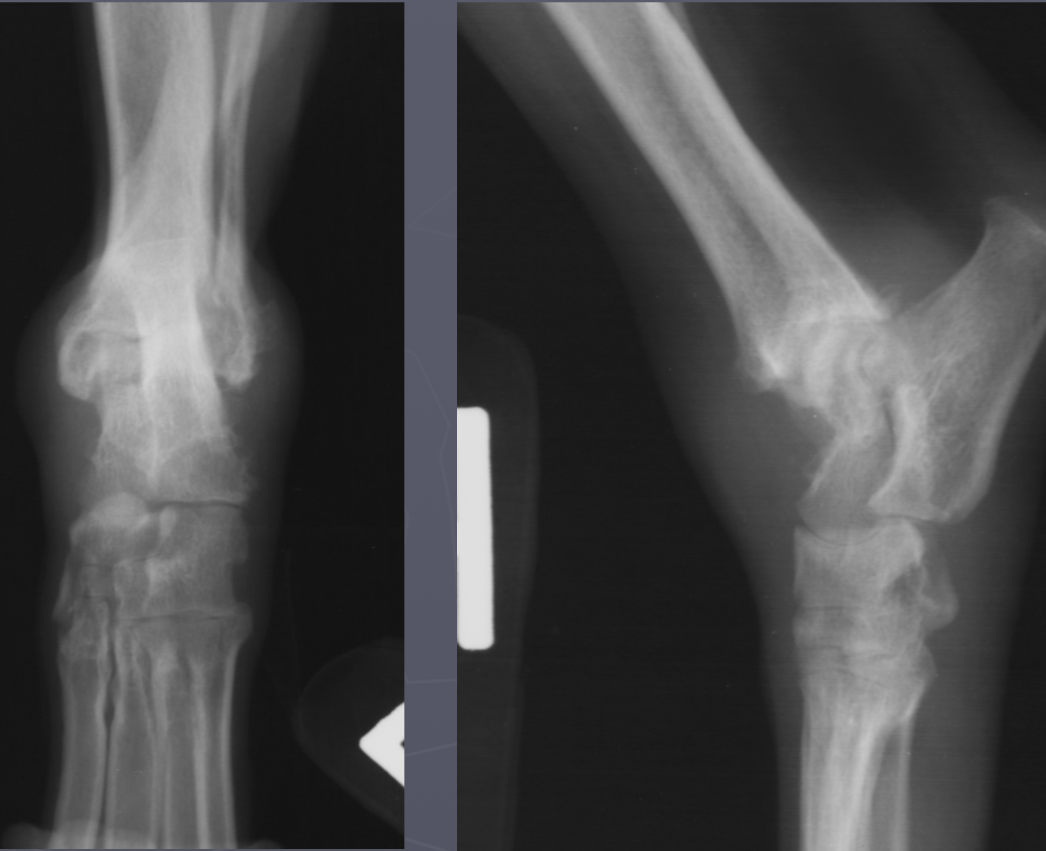

erosive polyarthritis/rheumatoid arthritis signalment

AGG lesion

small breeds -shetland sheepdog and poodle

greyhounds

cats get a proliferative polyarthropathy

swelling, cyst like lucencies, destroyed joint surface

± multiple bones

erosive polyarthritis

non-erosive polyarthritis signalment/lupus

just soft tissue swelling

multiple joints involved

NO lysis

non-erosive polyarthritis

joint tumor signalment

middle/large breed dog

stifle and elbow joints

cross the joint

joint associated tumor